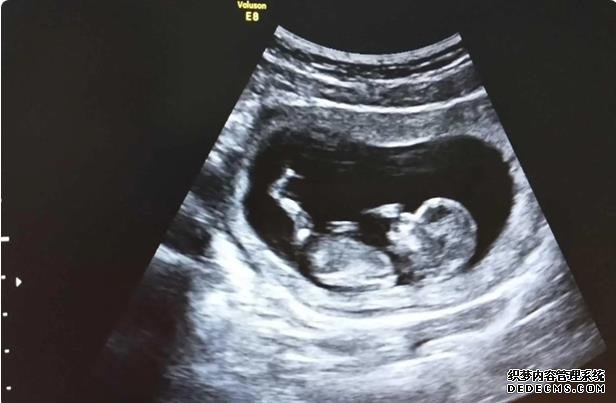

10天回醫院抽血我懷上了,我既然懷上了,血值475.這會我還是不相信我覺得沒那么容易,回家繼續安胎,14天后一超,有胎芽了,存活了?繼續回家安胎7天二超,胎兒一切正常,再回家安胎,14天三超胎兒長的很好!畢業的時候懷孕差不多兩個月!然后回家安胎第一次產檢胎兒一切正常,每次看到b超圖那個小人兒心里那感覺,所有的報告正常,應該好多像我這樣的人都會對著報告傻笑!心里那開心!開心接下來就是等早唐報告一個禮拜出來,報告結果一切正常!回家安心等中唐啦!其實等待的過程心里都是很擔心,怕寶寶哪里不正常的!我真后悔當初不一早直接做試管!